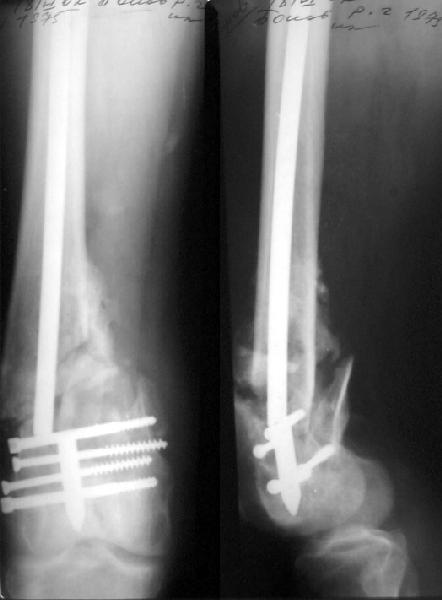

Такой вариант мы не рассматривали как чрезмерно травматичный. Как и предполагали, удалось сопоставить отломки стержня и после удаления

винтов вытолкнуть нижний кусок дистально. И через это же отверстие, используя стандартный доступ с расщеплением сухожилия 4-главой мышцы,

ретроградно забили другой стержень диаметром опять 11 мм - толще у нас пока таких нет. Обнадеживает то, что диаметр утолщенной части стержня 12 мм, а отверстие - 5 мм.

If we should look for "hairs in an egg", we can see that distal fragment is a little flexed and (perhaps) valgus.

First deviation could be corrected by removing at first the screw with black arrow.

Another little imperfection is the small size of the nail and large holes (see the other black arrows) just on the fracture line : these mechanically make the nail less resistant and, if weigh bearing is full, they could be a cause of failure.

If your patient will be prudent, fracture will heal very well.

You said: " but inserted from below. I locked it statically at the moment."

I have a query. From the picture it looks as if you used the usual proximal end as the distal end of nail.